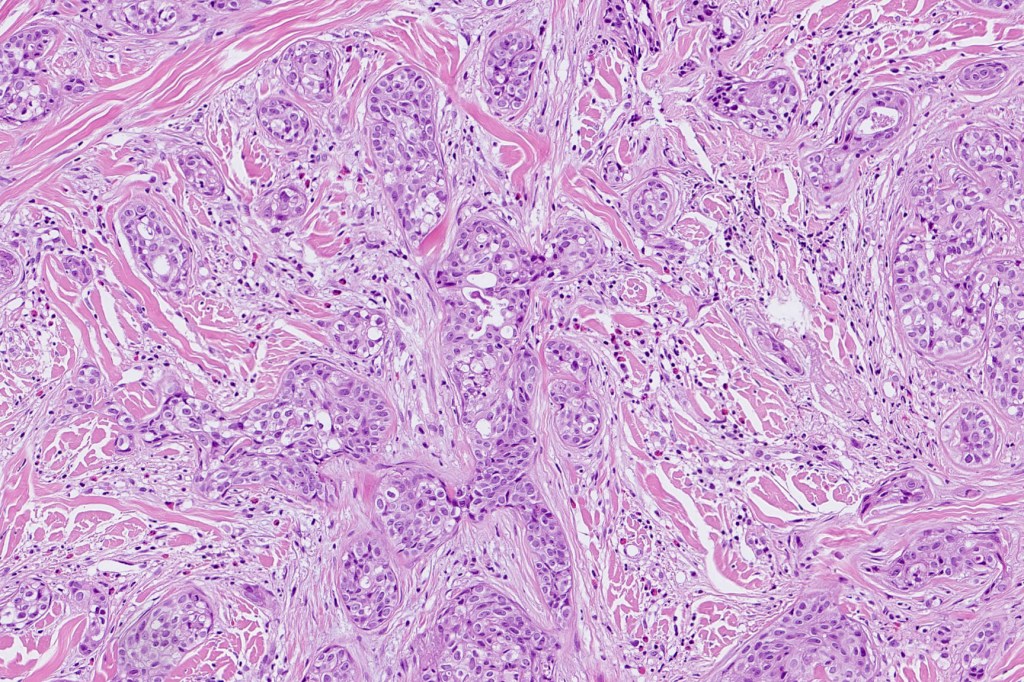

•Widely infiltrating biphasic tumor

•Superficial SCC

•Adenocarcinoma in deeper reaches

•Variable pleomorphism and mitotic activity

•Deep part may show both ducts and glands

•Often extends to the subcutaneous fat

•Perineural infiltration is commonly seen